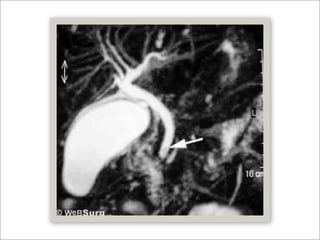

Generalidades

   TAC

 Sensibilidad 65 - 93%

 Especificidad 84 – 100%

   Colangioresonancia (MRCP)

   Sensibilidad y especificidad mayor al 90%

   Ultrasonido Endoscópico (EU)

   Sensibilidad y especificidad mayor al 95%

Generalidades  TAC  Sensibilidad 65 - 93%  Especificidad 84 – 100%  Colangioresonancia (MRCP)  Sensibilidad y especificidad mayor al 90%  Ultrasonido Endoscópico (EU)  Sensibilidad y especificidad mayor al 95%  Polkowski M, Helical computed tomographic cholangiography versus endosonography for suspected bile duct stones, Gut 1999;45:744–9.  Demartines N, Evaluation of magnetic resonance cholangiography in the management of bile duct stones. Arch Surg 2000;135:148–52.